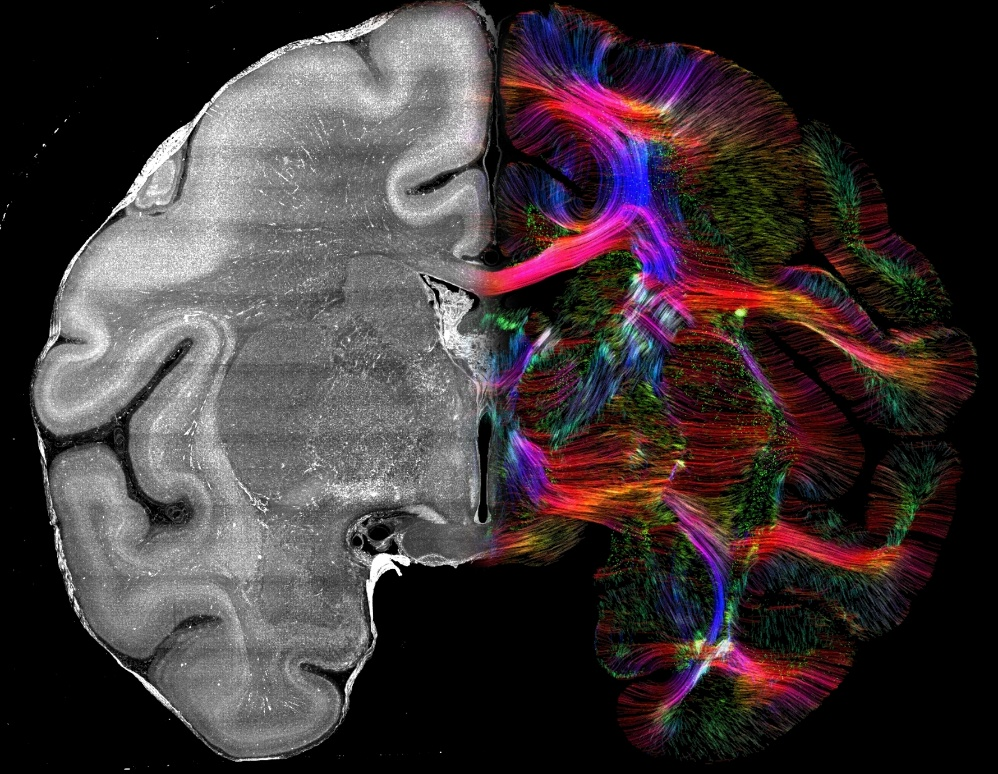

图2. 左侧是尼氏染色的猕猴脑切片,右侧是尼氏染色经过CABLE计算得到的纤维图像(颜色编码表示不同方向:红色代表左右向,绿色代表前后向,蓝色代表上下向)

研究人员发现,在尼氏染色等常规组织学染色下,神经细胞与胶质细胞的胞体和细胞核呈椭球形,其长轴指向并非随机,而是具有局部的一致性(视频1),研究人员称之为细胞构筑朝向一致性(cytoarchitectonic orientation coherence)。进一步研究发现通过空间转录组、抗体染色等方法标记的不同类型的神经细胞与胶质细胞,均具有细胞构筑朝向一致性。这种细胞朝向与邻近纤维束的走向一致,都受到脑内空间限制与挤压等约束,就像玻璃上的雨滴沿重力和气流的方向被拉长一样(图1)。CABLE技术通过计算图像梯度来提取这种细胞结构的方向性,再利用球面反卷积得到方向分布函数,进而利用dMRI中常用的纤维示踪算法(tractography)实现三维纤维追踪,从普通组织染色图像中反推出纤维结构网络(图2)。这种方法不依赖转基因或病毒标记,具有跨物种、跨平台的扩展能力。相较于基于水分子在轴突纤维中的扩散各向异性建立的弥散磁共振成像(dMRI)技术、基于髓鞘光学偏振各向异性建立的偏振光成像技术(PLI),此工作中基于细胞构筑朝向各向异性建立的CABLE技术具有更高的三维空间分辨率。